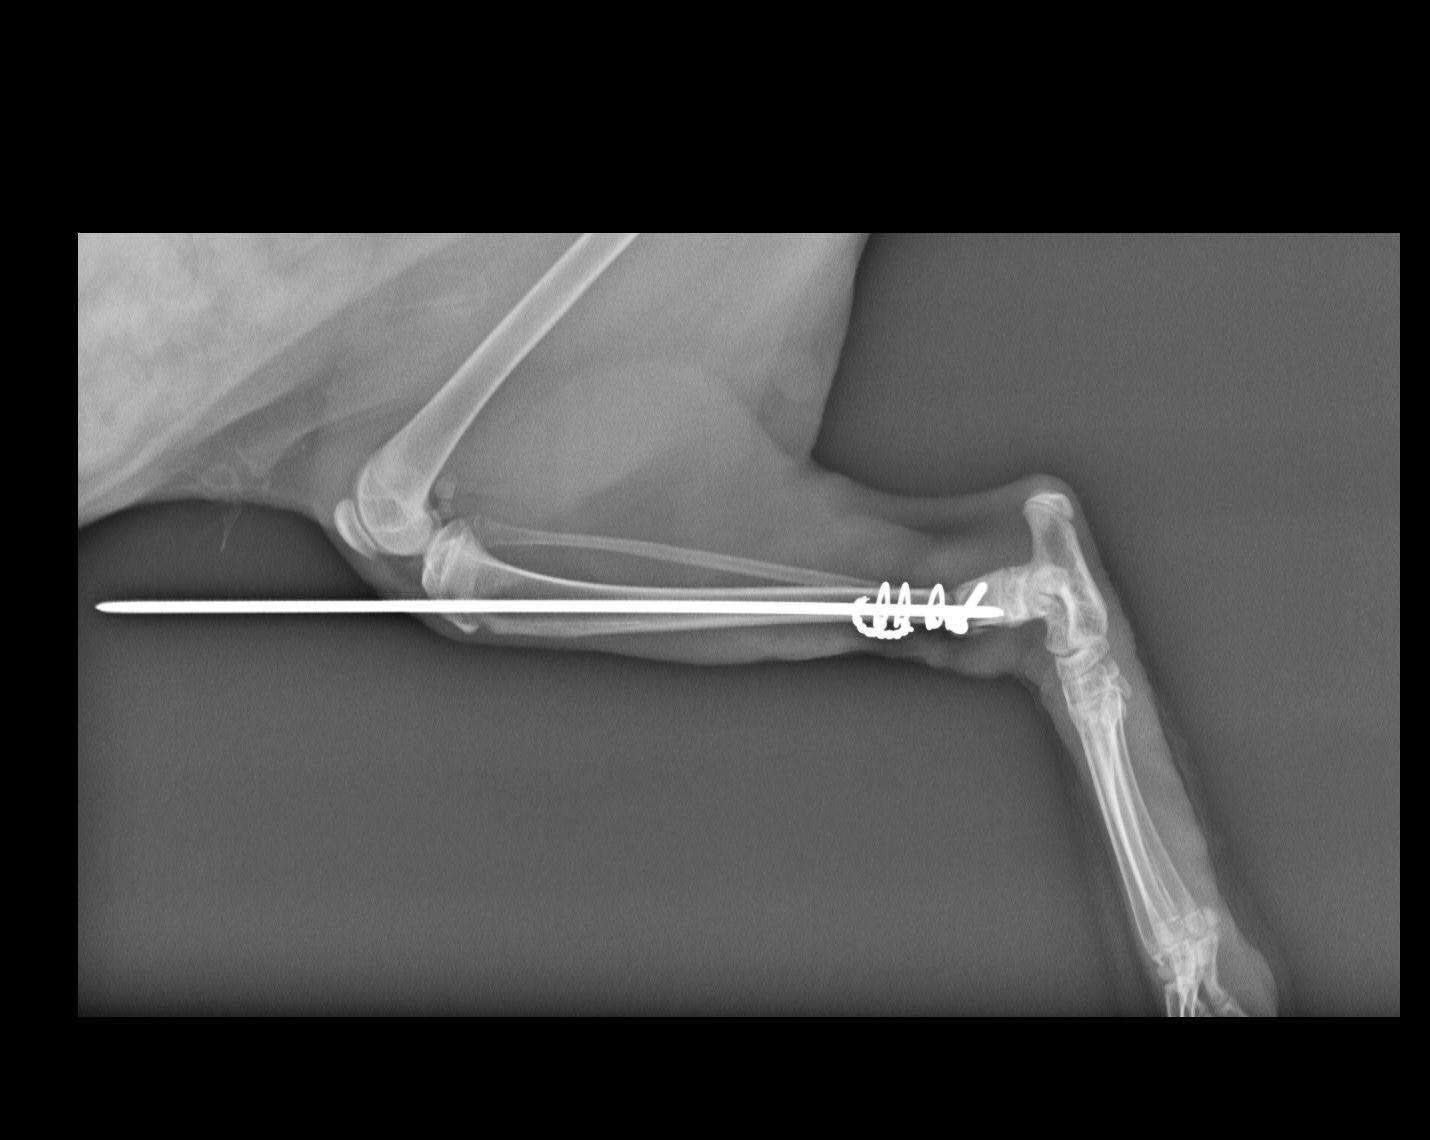

主題: 左後腳遠端脛骨骨折貓 申請者姓名: 孫美恩 花色: 申請日期: 2018-05-03 01:02:30 申請者部落格: 申請者臉書網址: 所在縣市/合作醫院: 高雄市/小新動物醫院 治療費用: 16600元 需求人數: 36人 已結案 (2024-06-01 13:13:20) 報名人員: 斑比(已付款)、Lannie Lin x3(已付款)、小靜(已付款)、hank(已付款)、GreenFire(已付款)、Peace(已付款)、liumon(已付款)、Lee Mei Yi x2(已付款)、Tracy Kao x2(已付款)、毛毛(已付款)、薇薇安(已付款)、Emily(已付款)、謝文森(已付款)、A.HSU(已付款)、A.HSU、MinMinCatCat(已付款)、張嘉琪(已付款)、Hsin-Ying Lin(已付款)、JJ Chang(已付款)、JJ Chang(已付款)、Rachel Hsieh x2(已付款)、簡佑銘(已付款)、Kelly(已付款)、Rachel Chiu x2(已付款)、何瑋樺 x2(已付款)、Irene(已付款)、Jessie Chang(已付款)、靜小芳(已付款)、Sky Lin(已付款)、徐佩如(已付款)、 候補人員: 動物病情說明: 貴協會您好,我於住家附近看到一隻浪貓用三隻腳跳著走路行動緩慢,但因他生活地有許多浪狗出沒,而本身也有飼養貓咪,擔心他因為跛腳無法迅速行動而遭遇危險,於心不忍所以撈起就醫,而醫生判定貓咪是因為右後腿遠端脛骨斷裂無法行走需要開刀治療。但因為目前仍是學生,對於能支付的醫療費用實在有限,所以上到這個平台來求救,希望能申請到醫療補助,請求大家一起幫忙讓小貓能夠重新走路,謝謝您們。 動物近況說明: 目前開刀傷口已癒合,對腿部有以外包紥固定,並關籠避免過度活動。